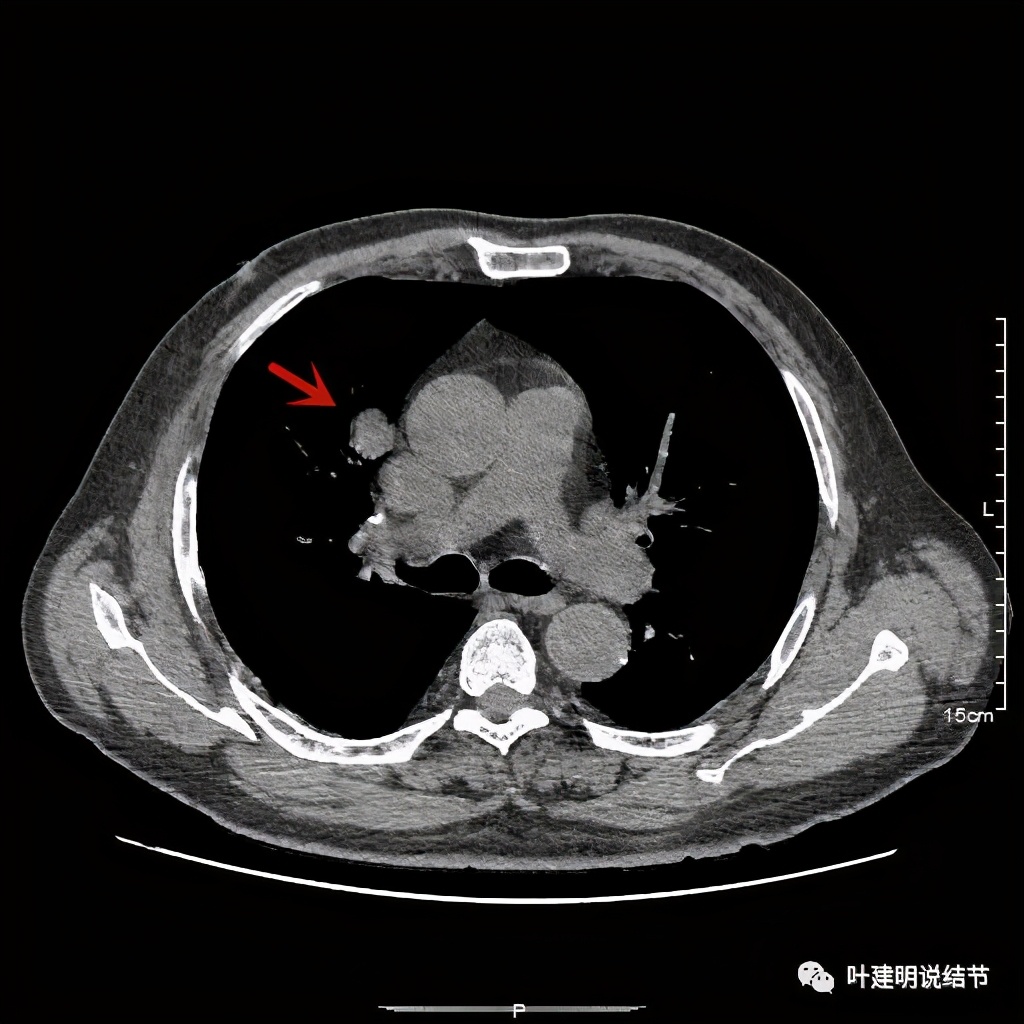

上图示病灶边缘过于光滑(绿色);血管贴边走行(桔色)

以上几图也示病灶边缘过光(绿色);血管贴边,感觉没受侵犯(桔色)

事前来看,达2.4厘米的不均质实性肿块,增强有轻度不均匀强化,血管贴边走行,支气管疑有截断,恶性不能除外,而且可能性较大。但现在经过手术已已经证实是错构瘤的情况下,我们回头来看,其实有许多不符合恶性的地方:

1、病灶的每个层面,边缘都过于光滑了。肺癌一般到这个大小总要有棘突、分叶、毛刺、牵拉周围胸膜等边缘异常的征象;

2、肿瘤大于2厘米以上,又紧贴血管,多有血管走行异常、受侵或血管进入等征象;